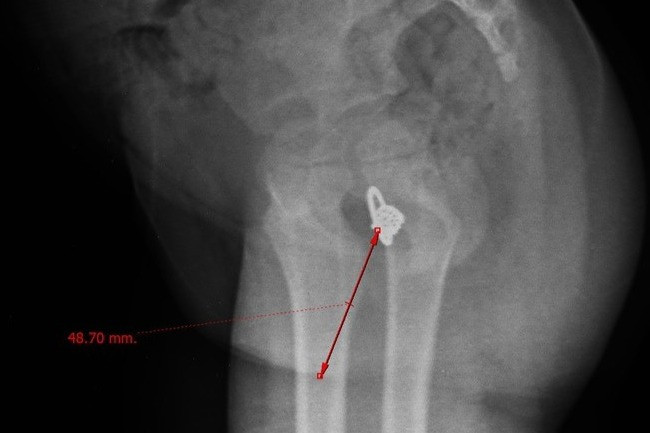

Ngày 15/3, PGS.TS Lê Thị Anh Đào, Trưởng Khoa Phụ ngoại (A5), cho biết qua thăm khám, các bác sĩ nhận thấy bệnh nhân bị ứ dịch âm đạo, kiểm tra màng trinh dầy, chỉ có một điểm thông nhỏ như điểm kim đâm, trào mủ. Hình ảnh chụp cộng hưởng từ cho thấy ứ dịch dạng mủ ở âm đạo và buồng tử cung.